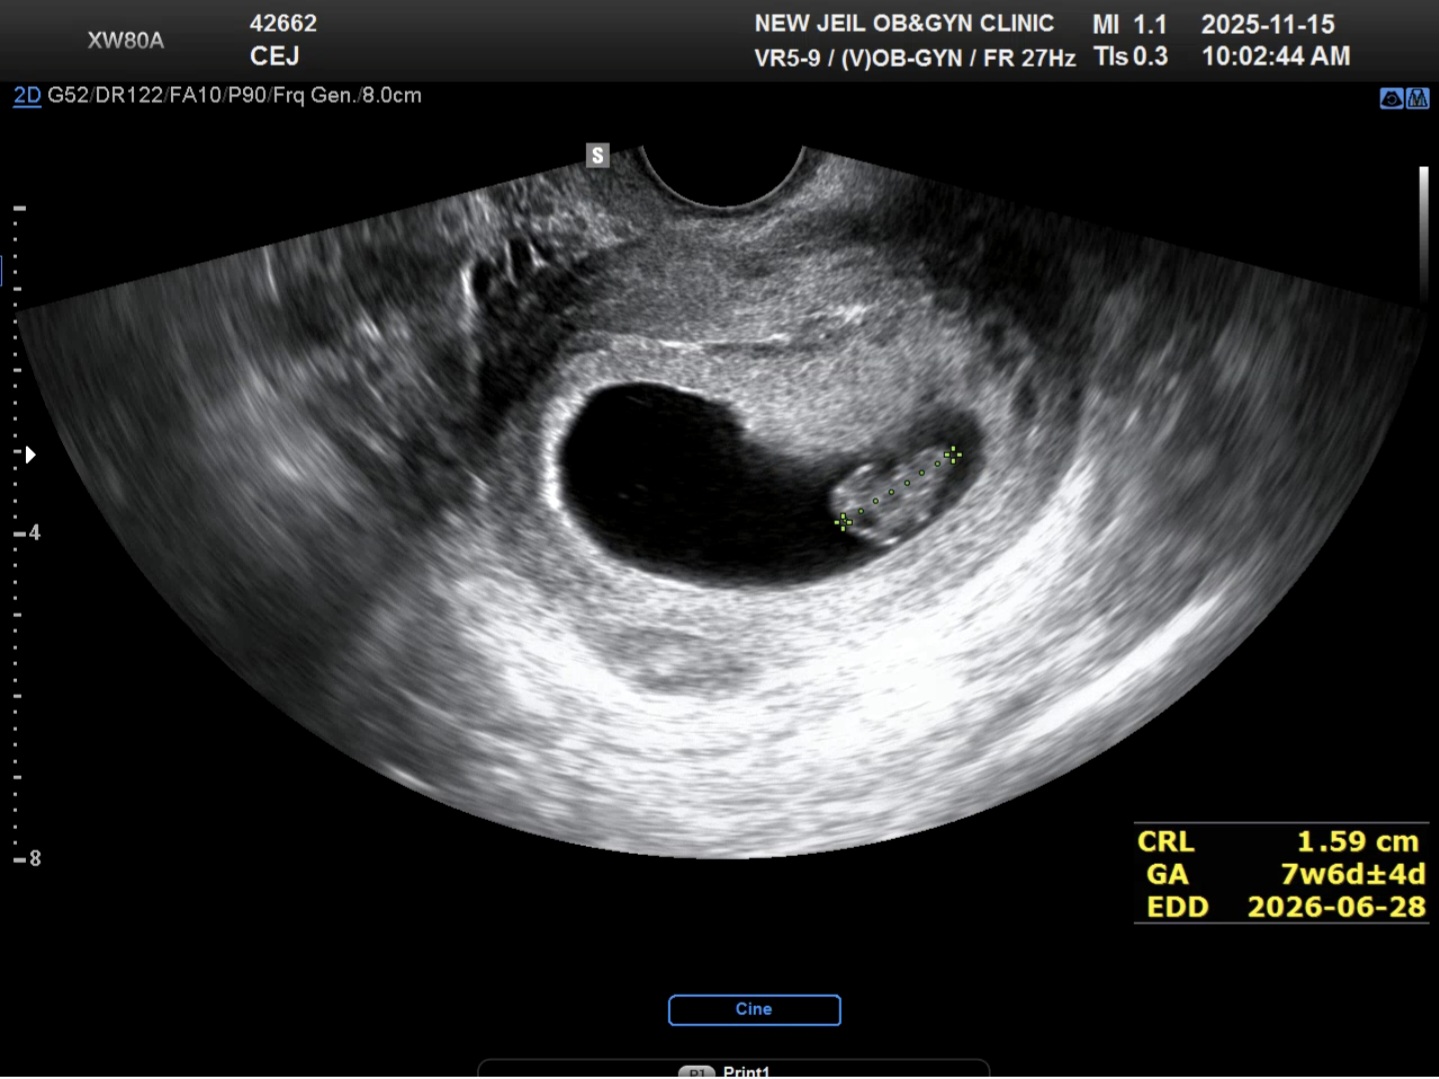

이틀 연속 오늘까지 3일 피비침이 있었어요. 검붉은 피도 보였고 갈색 분비물도 보였고요 평일에 병원을 갈 수가 없어서 오늘 내원 했는데 결론은 잘크고 있다 괜찮다였는데 제가 자궁후굴이라네요 허허허 자궁후굴은 임신기간동안에 전굴보다 아플거라는데 걱정이 좀 되네요;;

저도 피고임이나 다른 이상 보이지 않고 해서 방지제까지는 안써도 된다해서 그냥 돌아왔어요 허허 그리고 후굴자궁이라 피가 늦게 나온거다?같은 설명이었어요